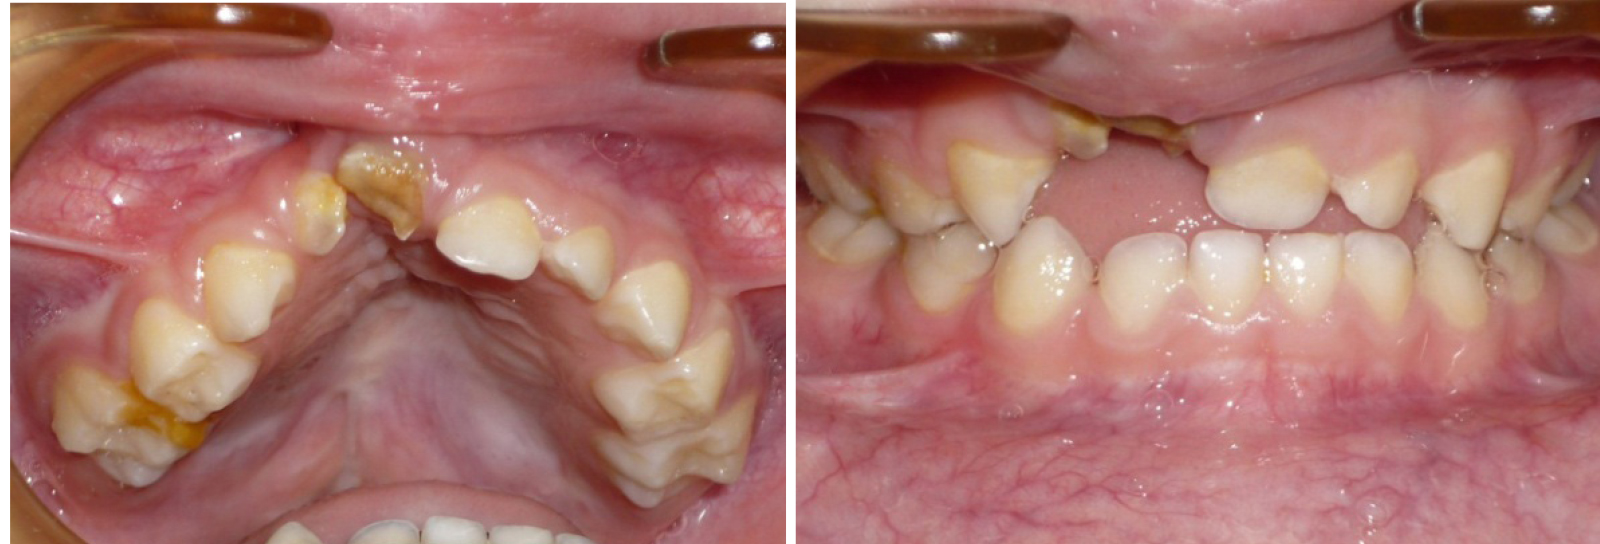

Эффективность предложенных методов графического построения прогнозируемых форм зубных арок определялась при анализе результатов лечения детей с врожденной аномалией в периоде молочного прикуса. С этой целью проведено лечение 15 детей с врожденным односторонним несращением губы и нёба. Практически во всех клинических случаях определялось сужение трансверсальных размеров, более выраженное в переднем сегменте арки. Окклюзия не соответствовала признакам физиологической нормы. Отмечалось укорочение глубины арки (рис. 2).

Рис. 2. Патологическая форма верхней зубной арки при врожденной аномалии

Анализ данных биометрии показал, что на стороне расщелины расстояние от условной сагиттали до молочного клыка составляло до лечения (11,52 ± 0,93) мм, а после лечения исследуемый параметр составлял (16,39 ± 0,64) мм (р ˂ 0,05). На котрлатеральной стороне разница в изменении положения клыка была не достоверной и в динамике лечения изменялась с (14,93 ± 0,79) до (16,27 ± 0,84) мм (р ˃ 0,05). Отмечалось изменение размеров диагоналей переднего сектора дентальных арок (клыковых диагоналей), которые на стороне расщелины в динамике изменялись от (13,34 ± 0,96) до (18,27 ± 0,71) мм (р ˂ 0,05). На контрлатеральной стороне исследуемый показатель изменялся с (16,73 ± 0,87) до (18,12 ± 0,95) мм (р ˃ 0,05). Диагонали зубных дуг (центрально-молярные) с обеих сторон после лечения составляли по (35,52 ± 1,13) мм.

Таким образом, с учетом полученных данных было сделано заключение об эффективности графической репродукции дентальной арки молочного прикуса при лечении детей с аномалиями зубных дуг.